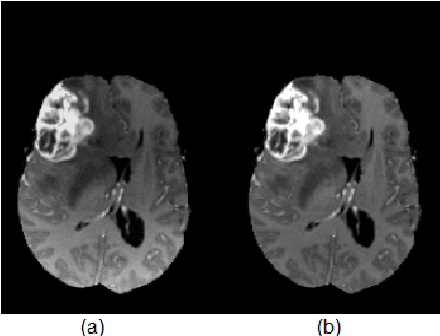

Abstract:Detection of brain tumor using a segmentation based approach is critical in cases, where survival of a subject depends on an accurate and timely clinical diagnosis. Gliomas are the most commonly found tumors having irregular shape and ambiguous boundaries, making them one of the hardest tumors to detect. The automation of brain tumor segmentation remains a challenging problem mainly due to significant variations in its structure. An automated brain tumor segmentation algorithm using deep convolutional neural network (DCNN) is presented in this paper. A patch based approach along with an inception module is used for training the deep network by extracting two co-centric patches of different sizes from the input images. Recent developments in deep neural networks such as drop-out, batch normalization, non-linear activation and inception module are used to build a new ILinear nexus architecture. The module overcomes the over-fitting problem arising due to scarcity of data using drop-out regularizer. Images are normalized and bias field corrected in the pre-processing step and then extracted patches are passed through a DCNN, which assigns an output label to the central pixel of each patch. Morphological operators are used for post-processing to remove small false positives around the edges. A two-phase weighted training method is introduced and evaluated using BRATS 2013 and BRATS 2015 datasets, where it improves the performance parameters of state-of-the-art techniques under similar settings.